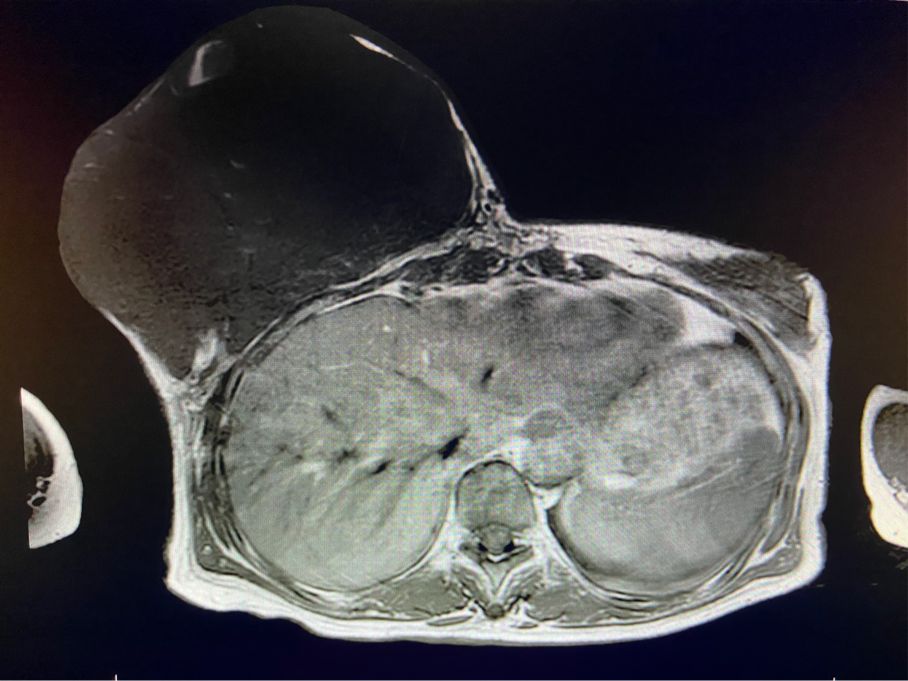

2周前,王女士的右乳外下方皮膚破潰,伴大量滲液,還發(fā)出陣陣惡臭。經(jīng)多方打聽(tīng),王女士從外地來(lái)到西安國(guó)際醫(yī)學(xué)中心醫(yī)院甲乳外科劉曉敏主任處就診。入院后,迅速完善了一系列相關(guān)術(shù)前檢查:王女士的雙乳外形不對(duì)稱,右乳約22?20cm,皮膚水腫明顯并可見(jiàn)靜脈曲張。右乳外下象限皮膚可見(jiàn)局部破潰,創(chuàng)面有3處,共約6?4cm大小,創(chuàng)面呈暗紅色,伴有血性滲出及惡臭,局部皮膚溫度升高。右側(cè)腋窩可觸及腫大淋巴結(jié)。

該患者右乳巨大腫物術(shù)前初步考慮乳腺葉狀腫瘤可能,因腫瘤太大,幾乎遍及整個(gè)右側(cè)乳房,為保證“無(wú)瘤原則”,術(shù)中切除范圍位置未知,極有可能出現(xiàn)皮瓣缺損。于是,經(jīng)過(guò)和整形醫(yī)院郭樹(shù)忠院長(zhǎng)、整形外科王愛(ài)武主任的討論,提供了兩種手術(shù)方式,一是創(chuàng)面修復(fù)(植皮或轉(zhuǎn)移皮瓣修復(fù)創(chuàng)面),二是乳房再造,與患者及家屬溝通后,決定先解決腫物,3年病情不再?gòu)?fù)發(fā)后,可以再考慮乳房重建。